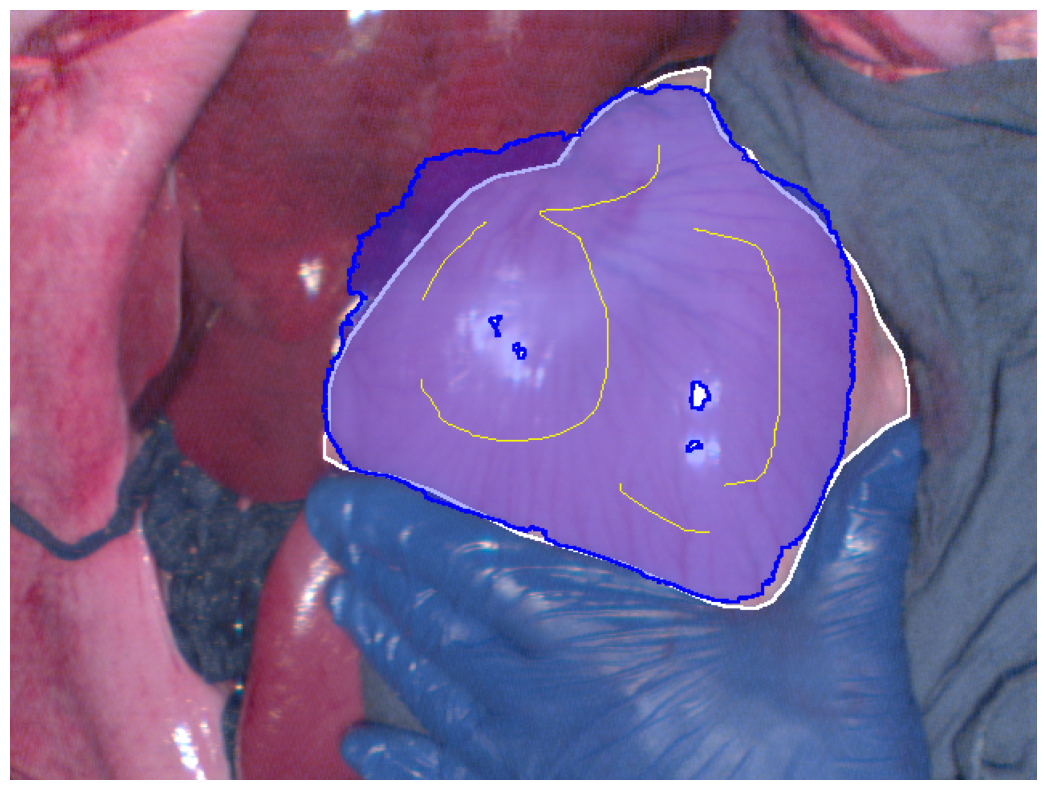

Refer to caption

(d) Euclidean distance map best Dice segmentation result

Figure 2: Segmentation results (blue regions) at the best Dice coefficient for different methods and ground truth (white regions), along with the curves of Dice coefficient variation with threshold adjustments.

In Fig. 2, the segmentation results at the best Dice for the four different methods are displayed, along with the variation in Dice coefficients with threshold adjustments. From Fig. 2e, it can be seen that the Euclidean distance method has the lowest maximum Dice score of 0.914. The methods using geodesic distance maps generated from hyperspectral images and reconstructed RGB images achieve similar maximum Dice values, both higher than the Euclidean method. The deep learning-based feature geodesic distance map method achieves the highest maximum dice coefficient.

For the 575 images in P086, automated scribbles were generated by skeletonizing the annotation results, and segmentation results were produced using pre-mentioned four different methods. Among these, the deep learning-based feature geodesic distance map method achieved the highest average max Dice score of 0.842, demonstrating its superior performance.